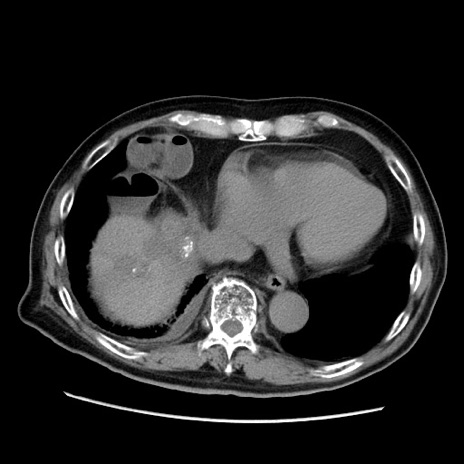

症例21(横断像)

【症例】70歳代男性

【主訴】腹痛

【現病歴】肝硬変・肝細胞癌にてかかりつけの方。約9時間前に食後より腹痛出現。症状が徐々に増悪し、嘔吐出現したため来院。

【既往歴】肝硬変、肝細胞癌(RFA、TACE後)

【身体所見】意識清明、表情苦悶様、BT 36℃、BP 129/78mmHg、P 88bpm、SpO2 97%(RA)、右上腹部から心窩部にかけて圧痛あり、反跳痛なし、筋性防御あり。

【データ】WBC 5800、CRP 0.16